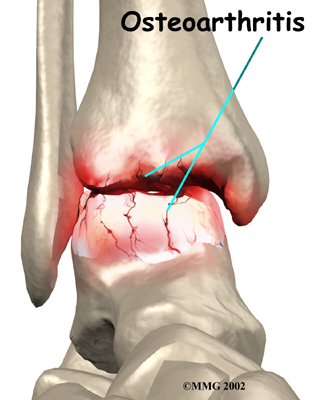

Injury to a joint, such as a bad sprain or fracture, can cause damage to the articular cartilage. The cartilage can be bruised when too much pressure is exerted on it. This damages the cartilage, although if you look at the surface it may not appear to be any different. The injury to the material doesn't show up until months later. Sometimes the cartilage surface is damaged even more severely, and pieces of the cartilage are ripped from the bone. These pieces do not heal back and usually must be removed from the joint surgically. If not, they may float around in the joint, causing the joint to catch and be painful. These fragments of cartilage may also do more damage to the joint surface.

Once this cartilage is ripped away, it does not normally grow back. Unlike bone, holes in the surface are not simply replaced by the cartilage tissue around the hole. Instead the defects are filled with scar tissue. The scar tissue that forms is not nearly as good a material for covering joint surfaces as the cartilage it replaces. It just can't support weight and isn't smooth like true articular cartilage.

Over many years this imbalance in the joint mechanics can lead to damage to the articular surface. Since articular cartilage cannot heal itself very well, the damage adds up. Finally, the joint is no longer able to compensate for the increasing damage, and it begins to hurt. The damage occurs well before the pain begins.

Pain is the main problem with arthritis of any joint. This pain occurs at first only related to activity. Usually, once the activity gets underway there is not much pain, but after resting for several minutes the pain and stiffness increase. Later, when the condition worsens, pain may be present even at rest. The pain may interfere with sleep. The joint may swell, fill with fluid, and feel tight, especially following increased activity. As the articular cartilage starts to wear off the joint surface, the joint may squeak when moved. Doctors refer to this sound as crepitation.